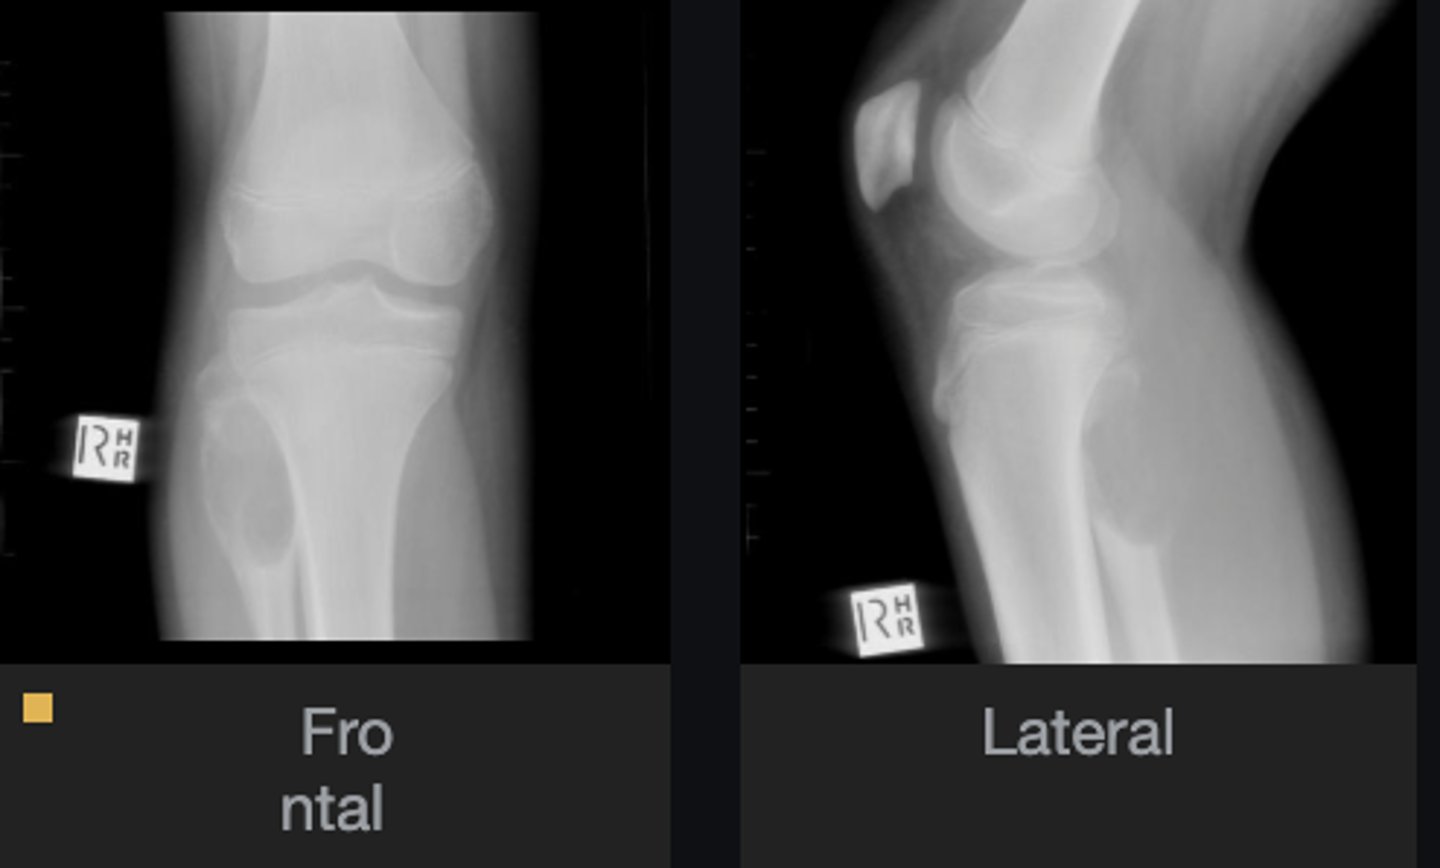

- Solitary

- Eccentric

- Geographic

- Multiloculated

- Fibrous matrix

- Small

- Cortical thinning

- Sclerotic border

Describe the lesion

<p>Describe the lesion</p>

Non-Ossifying Fibroma

Diagnosis?

Nothing

Next step?

<p>Next step?</p>

- Anterolateral distal tibia

- Metaphysis

- Septation

<p>Diagnosis?</p>

- Look for fracture

- Refer to orthopedist